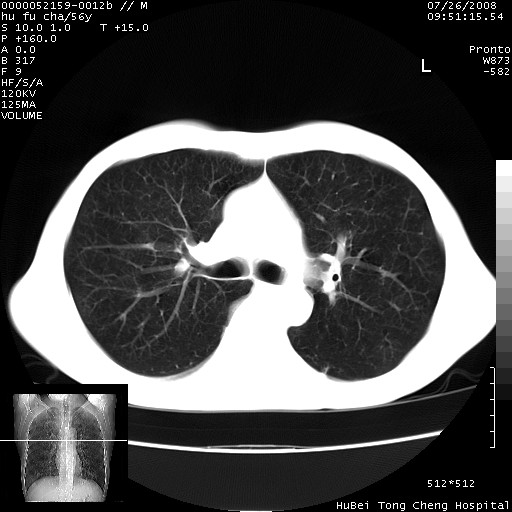

以下是引用zsl6918在2008-8-25 22:47:00的发言:[br]胸骨,胸椎及肋骨均可见多发转移表现,肝内低密度结节不除外转移。原发灶可能在右肺。双侧可见支扩表现。

以下是引用卜一在2008-8-26 8:02:00的发言:[br][br] 支持:肺癌并肺内,胸骨,胁骨,胸椎及肝内转移!另:左肺支气管扩张征伴感染! [br]

以下是引用zjzjr在2008-8-26 11:03:00的发言:[br]支持:肺癌并肺内,胸骨,胁骨,胸椎及肝内转移!另:左肺支气管扩张征伴感染!